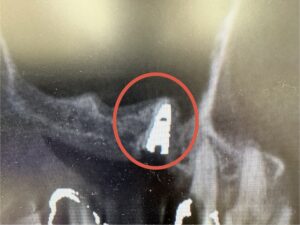

術後

拡大した術後すぐのレントゲン

CTによる診査・診断の結果、右上顎の骨量が不足していたため、骨造成を併用しながら“ソケットリフト法”を選択しました。

慎重に処置を進め、同日に安全にインプラント埋入まで行うことができました。